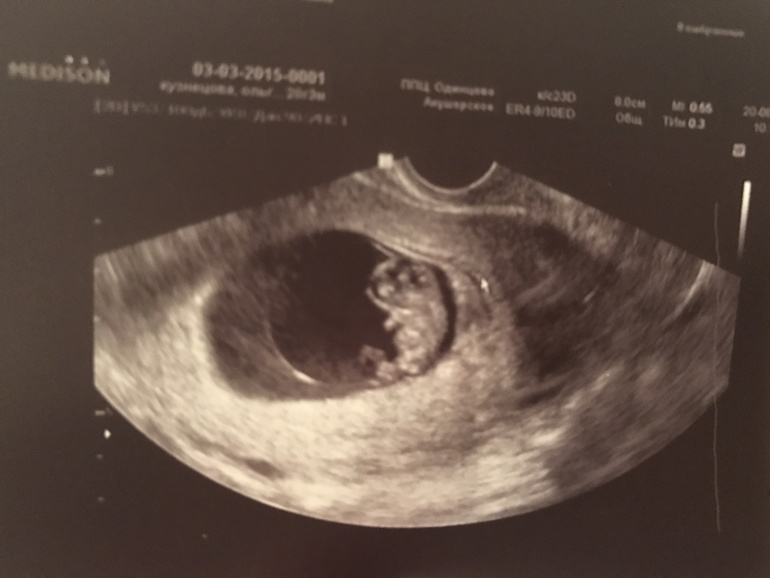

Результаты узи после кровянистых выделерий

УЗИ, КТГ, доплерС малышом все хорошо, в остальном организовавшаяся ретрохориальная гематома и предлежание хориона

И мое сокровище ❤️